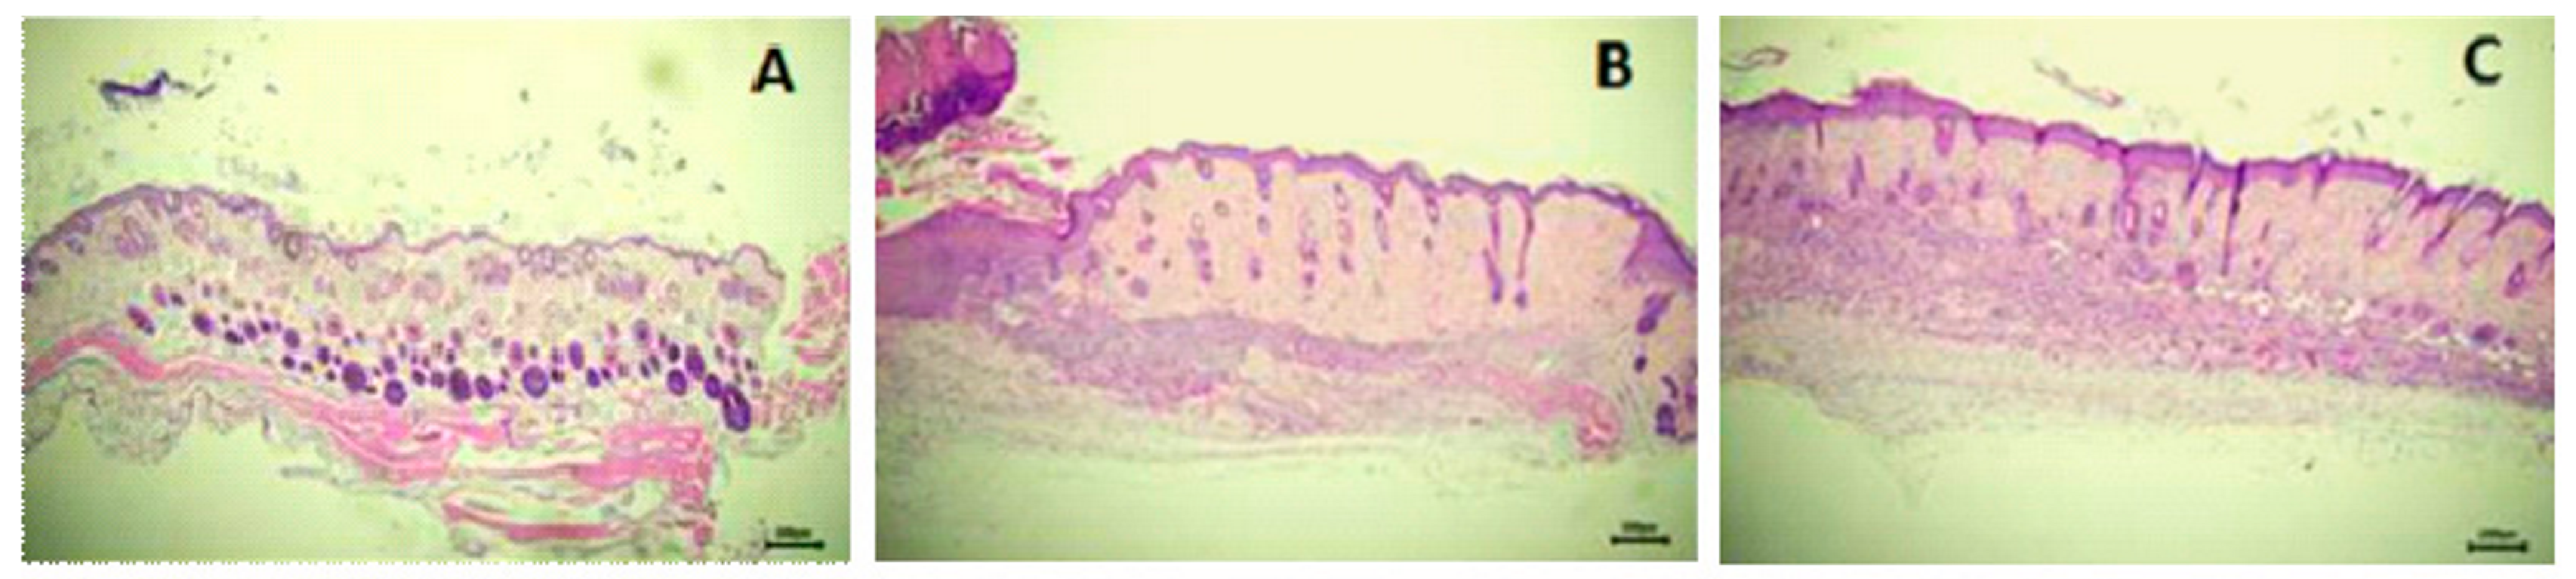

3.7. Wound-Healing Effect of AgNP in a Murine Incisional Acute Wound Model